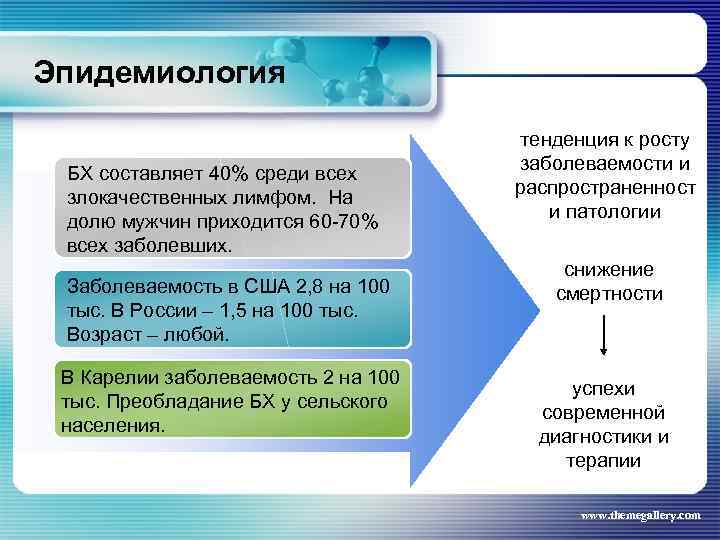

Эпидемиология БХ составляет 40% среди всех злокачественных лимфом. На долю мужчин приходится 60 -70% всех заболевших. Заболеваемость в США 2, 8 на 100 тыс. В России – 1, 5 на 100 тыс. Возраст – любой. В Карелии заболеваемость 2 на 100 тыс. Преобладание БХ у сельского населения. тенденция к росту заболеваемости и распространенност и патологии снижение смертности успехи современной диагностики и терапии www. themegallery. com

Эпидемиология БХ составляет 40% среди всех злокачественных лимфом. На долю мужчин приходится 60 -70% всех заболевших. Заболеваемость в США 2, 8 на 100 тыс. В России – 1, 5 на 100 тыс. Возраст – любой. В Карелии заболеваемость 2 на 100 тыс. Преобладание БХ у сельского населения. тенденция к росту заболеваемости и распространенност и патологии снижение смертности успехи современной диагностики и терапии www. themegallery. com